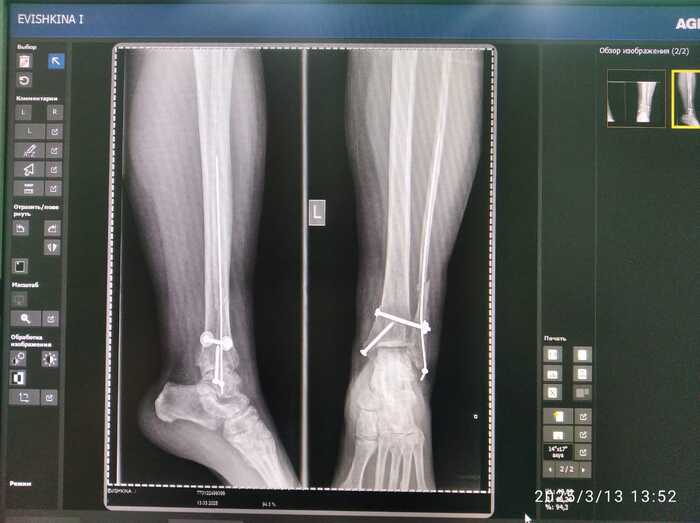

Мама сломала ногу 19 ноября 2024 года. Неудачно упала с дивана - перелом в трёх местах со смещением и разрывом связок. Ниже снимки сразу после операции

Поставили такие спицы. Прощу прощения, я не врач и могу неправильно употреблять некоторые термины.

Я сама живу далеко от неё и после новостей о переломе сходила в местную областную больницу за консультацией, где мне сказали, что от подобных "спиц" может наступить разрушение сустава и их нужно вытаскивать как можно быстрее (2-3 месяца после операции).

В конце февраря, 25 числа на осмотре врач сказал маме, что ей уже нужно ходить с тростью. Кость срослась неправильно, но пофиг, никакие спицы не нужно вытаскивать, так как связки не срослись. "Ждите хотя бы год и ходите без костылей."

-нужно вытаскивать поперечную спицу, так как связки уже зажили. И лечить артроз.

Ниже прилагаю сегодняшние снимки.

Upd: лечащий врач хочет вытащить всю конструкцию полностью.